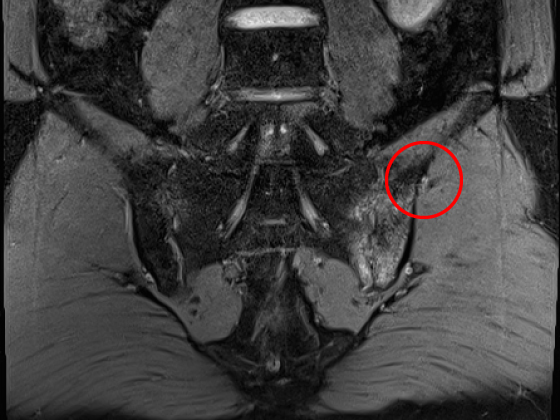

MRI 천장관절염

MRI

초기 병변은 X-ray에서 보이지 않는 경우가 있어, 조기 진단 시 MRI가 매우 중요합니다.